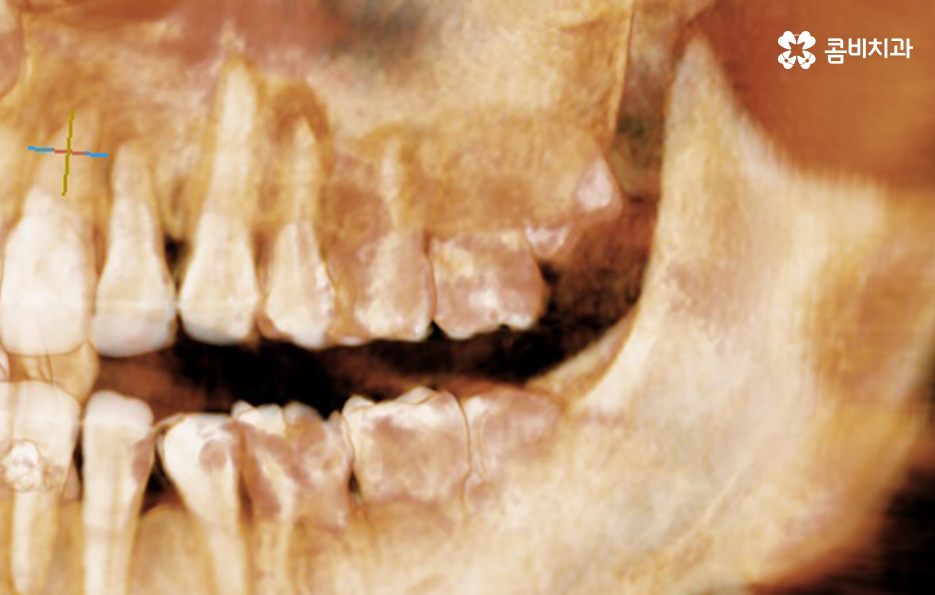

사랑니는 치아 중에서도 가장 마지막에 맹출이 되며 현대인들은 턱뼈가 좁아지는 추세이기 때문에 마지막에 자라는 사랑니는 위 케이스처럼 윗니의 경우 어금니의 높이 보다 다소 낮게 자라는 경우가 많고 아랫니의 경우 매복되어 있거나 누워서 자라는 사랑니의 형태로 자라는 경우가 많이 있는데요. 이러한 사랑니의 형태로 인해 어금니와 사랑니 사이에 이물질이 끼기 쉽고 칫솔질이 잘 닿지 않기 때문에 충치 뿐 아니라 잇몸 염증이 발생되는 경우가 많으며 사랑니 어금니 통증의 원인이 주변의 세균 증가로 인해 충치로 이가 썩은 경우부터 잇몸이 자주 붓고 염증이 심해지면서 통증을 느끼는 경우가 40,50대 이후에 흔하게 발생되는 사랑니와 인접한 어금니의 문제로 볼 수 있어요

일반적으로 30대 이후에는 치주질환이 급증하게 되는데 40,50대 이후에는 잇몸이 점점 내려 앉게 되고 부분적으로 맹출된 사랑니 주변 잇몸 역시도 조금씩 내려앉는 경우가 많이 있는데요. 사랑니 사진을 보시면 아시겠지만 일반적인 치아의 높낮이와는 달리 사랑니가 어금니의 뿌리 부분 정도 높이에 자리하고 있는 것을 볼 수 있어요.

일반적인 치아와 치아 사이는 이물질이 쉽게 침투하지 못하게 치아 사이의 공간이 많지 않고 치아 역시도 실링이 되어 있어서 미생물이 치아를 쉽게 뚫지 못하며 면역 물질로 인한 면역 작용도 있기 때문에 평소 칫솔질과 치실 사용, 주기적인 스케일링으로 어느정도 관리가 될 수 있는 것에 반하여 사랑니의 경우 어금니의 뿌리 부분에 가깝게 충치가 발생하기 쉽기 때문에 적절한 치료 시점을 놓치면 사랑니 어금니 통증이 두 치아 모두를 발치하게 되는 상황까지 발생될 수 있어요